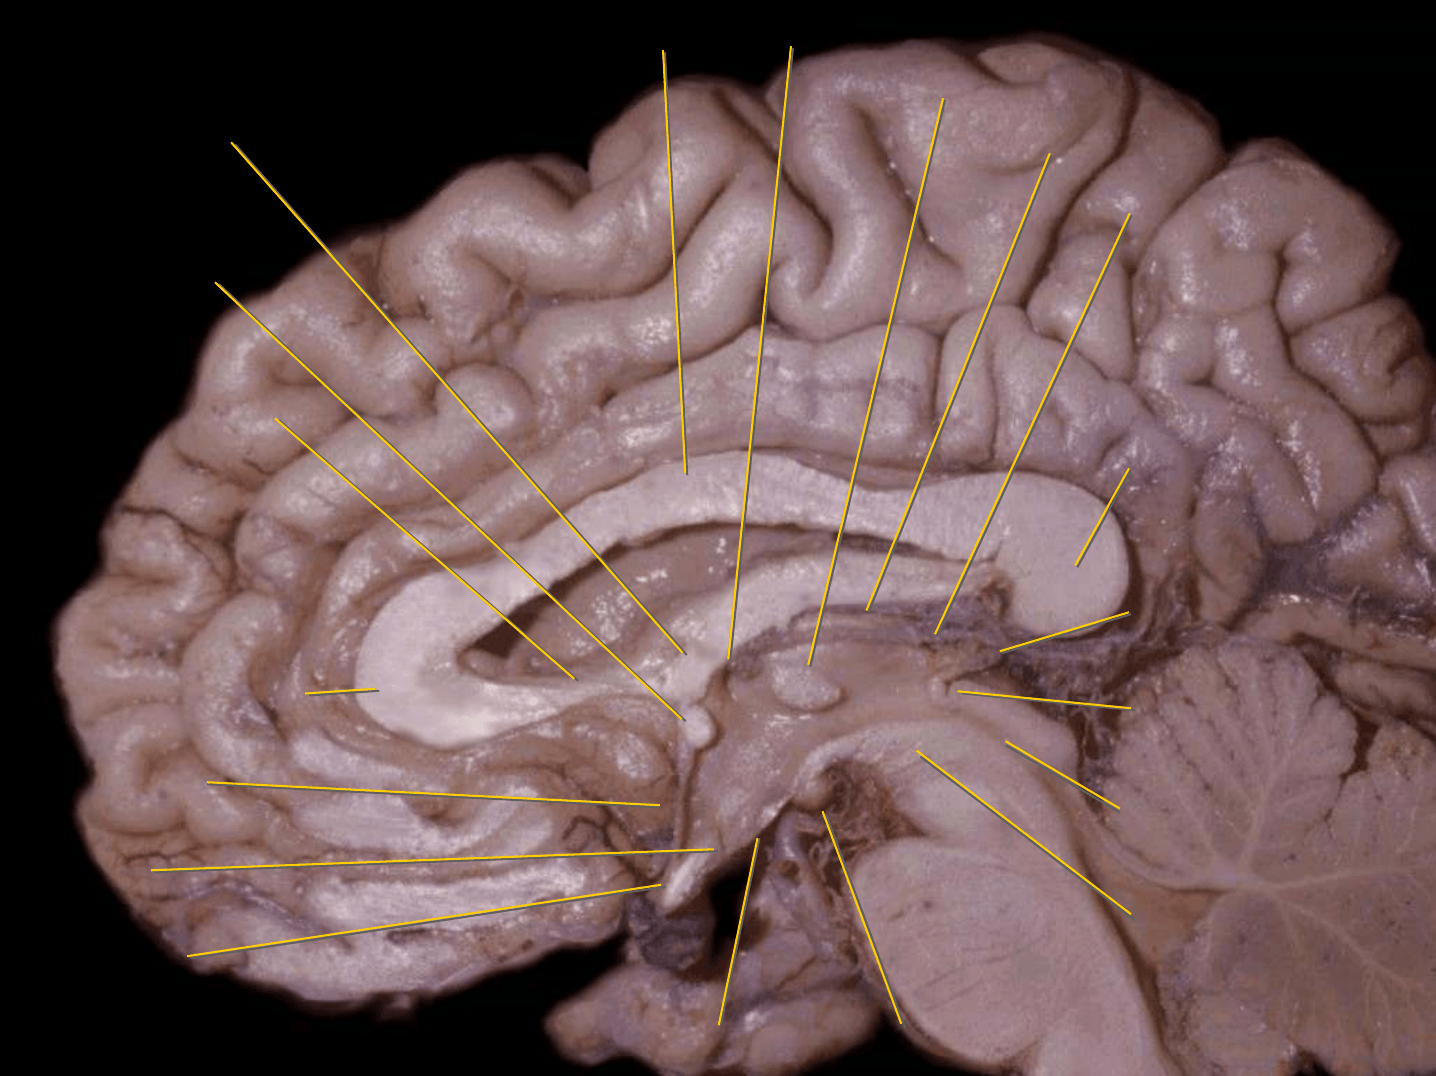

Tronco del cuerpo calloso

Rodilla del cuerpo calloso

Columna del fórnix

Comisura anterior

Foramen interventricular

Infundíbulo

Habénula

Pico del cuerpo calloso

Acueducto del mesencéfalo

Estría medular del tálamo

Adhesión intertalámica

Lámina terminal

Quiasma óptico

Tubérculo mamilar

Comisura posterior

Glándula pineal

Rodete del cuerpo calloso

Calota mesencefálica

Túber cinereum